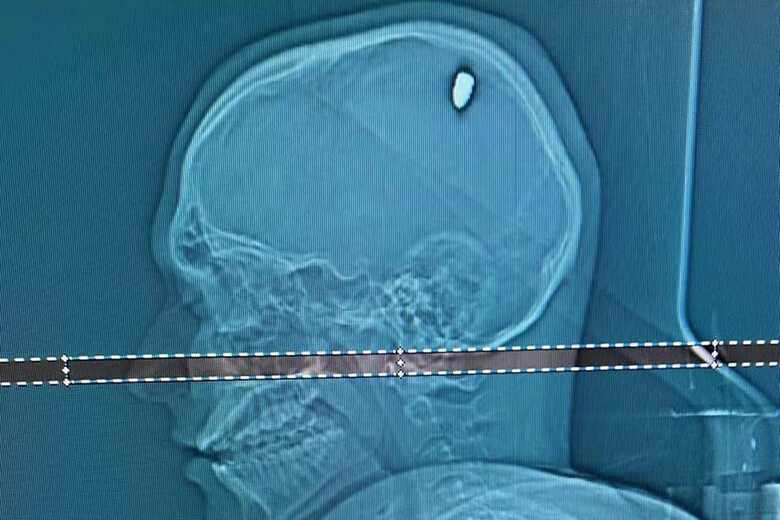

Ao procurar ajuda médica, uma tomografia revelou que Mateus estava com uma bala alojada na cabeça. Ao g1, o neurocirurgião Flávio Falcometa explicou o ferimento. “Parte dela penetrou no cérebro. Isso causou compressão da região, e os movimentos involuntários do braço.”